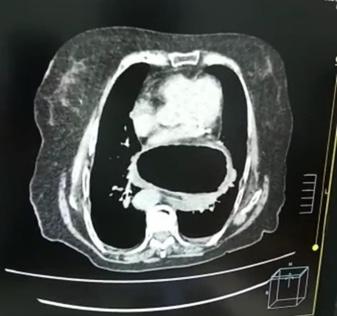

E. La exposición de un paciente es importante debido a las lesiones que se podrían omitir al estar en áreas no visibles. Posteriormente, es necesario el calentamiento del paciente, ya que la hipotermia puede contribuir a la aparición de complicaciones sistémicas, como las coagulopatías (10). No se debe olvidar la importancia de los estudios complementarios, como la radiografía portátil, la ecografiaFAST, que presenta una mayor sensibilidad para detectar neumotórax en comparación con la radiografía; 48,8 % vs 20,9 % (11). Además, la tomografía computarizada, electrocardiograma y laboratorios como el lactato sérico y el déficit de bases en la gasometría que se correlacionan con la mortalidad (12). Después de la evaluación primaria, se determinará si el paciente requiere una intervención quirúrgica de emergencia o se procederá a la evaluación secundaria, que consiste en una revisión detallada por sistemas y el uso de exámenes complementarios si es necesario. Con esta pequeña lectura creemos que se pueden realizar mas estudios locales para reflejar la importancia de la misma y preparar a mas estudiantes o profesionales en la atención de pacientes críticos.